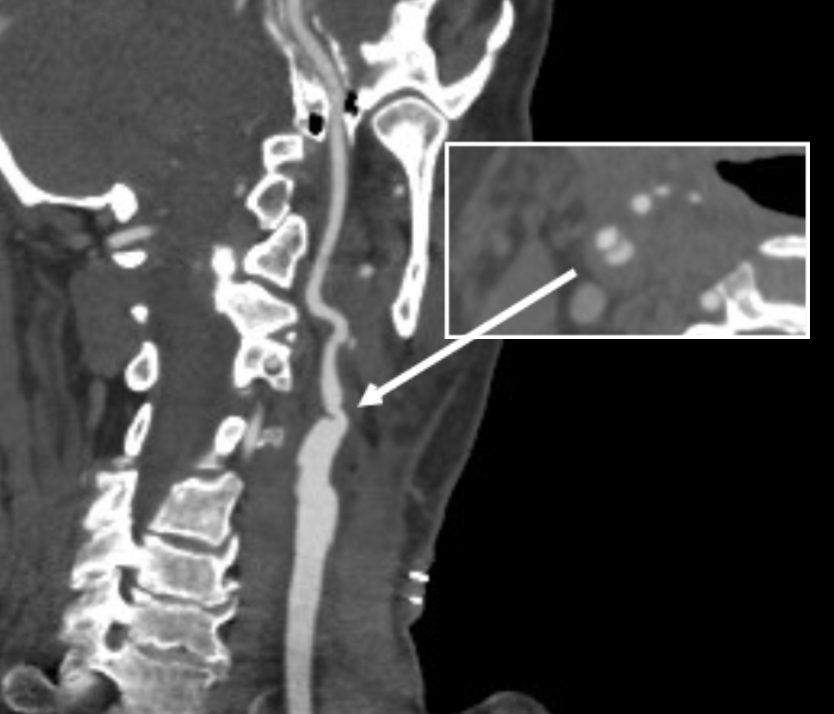

The patient recently returned for a 6 month followup. Duplex showed wide patency of her stent.

7 months post op.png